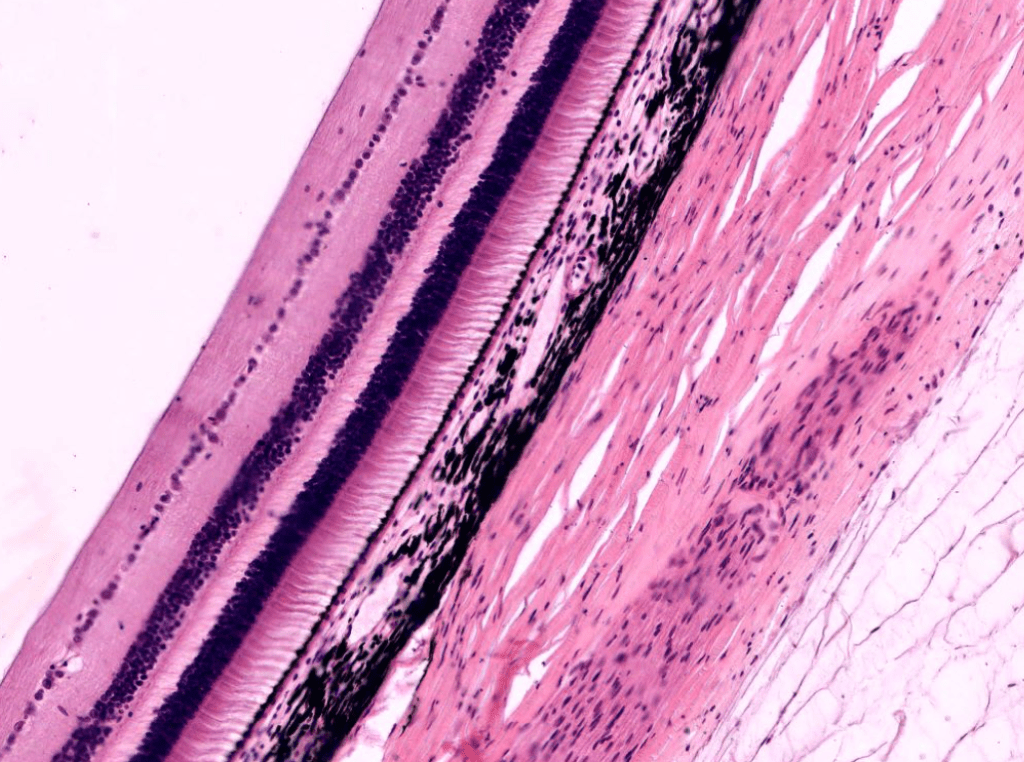

RETINA

- Epitelio pigmentario: Es la capa más externa de la retina.

- Capa de fotorreceptores: Está formada por los segmentos externos de los fotorreceptores.

- Limitante externa: No es una membrana, sino uniones tipo zónula adherens entre los fotorreceptores y las cél. de Müller.

- Nuclear o granular externa: Formada por los núcleos celulares de los fotorreceptores.

- Plexiforme externa: Sinapsis entre fotorreceptores y las cél. bipolares.

- Nuclear o granular interna: Encontramos núcleos celulares de las cél. bipolares, las cél. horizontales y las cél. amacrinas

- Plexiforme interna: Sinapsis entre células bipolares, amacrinas y ganglionares.

- Células ganglionares: Núcleos de las células ganglionares.

- Fibras nerviosas: Axones de cél. ganglionares.

- Limitante interna: Separa la retina del humor vítreo.